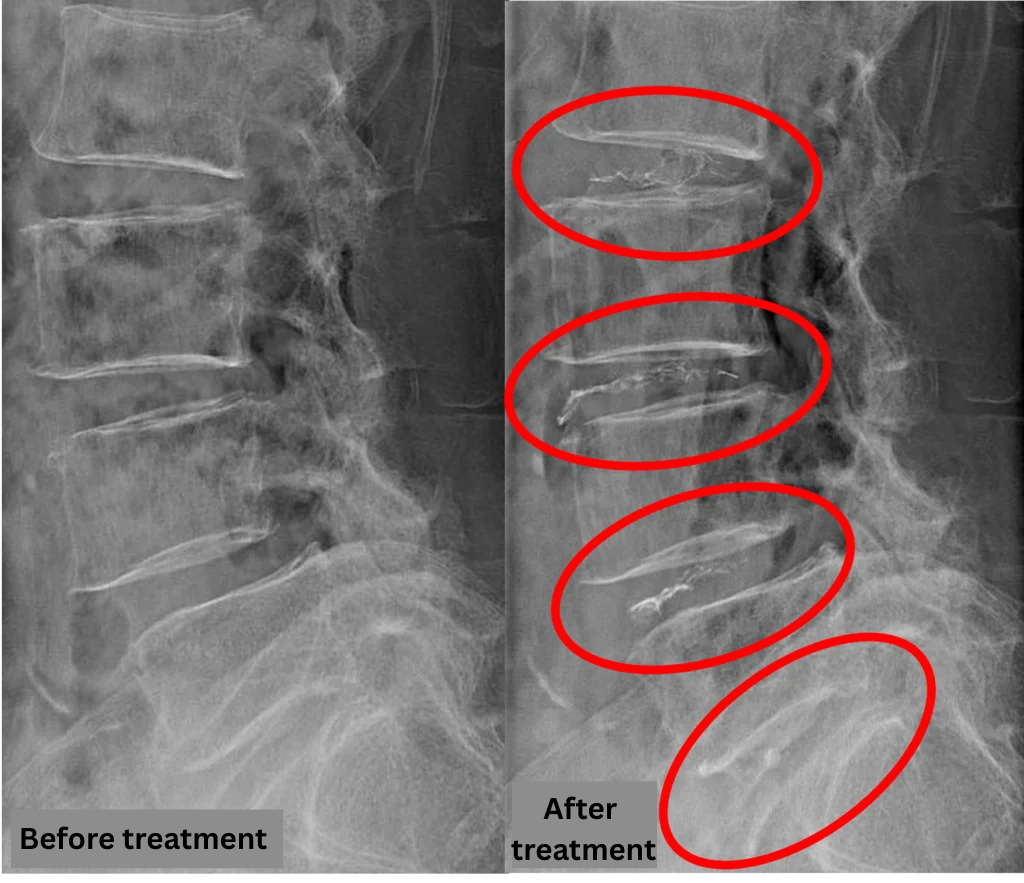

- L2/3, L3/4, L5/S: Intervertebral disc degeneration

- L4/5: Disc degeneration, bulging, and degenerative spondylolisthesis

The above findings were also observed on the imaging.

Compression of the spinal canal due to disc pathology at L2/3, L3/4, L4/5, and L5/S is highly suspected to be the primary cause of symptoms.

After consulting with the patient, the Cellgel Method was performed on L2/3, 3/4, 4/5 and 5/s.